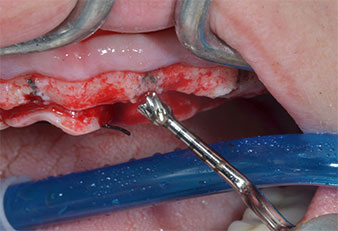

Uno strumento piezoelettrico (Piezomed I1) a forma di fiamma, rivestito in diamante, è stato usato per contrassegnare le posizioni dell'impianto e per eseguire una preparazione pilota (Fig. 3). Si è prestato attenzione a utilizzare un movimento verticale ascendente e discendente, con potenza ridotta, irrigazione completa e bassa pressione (inferiore a 300 g). Successivamente è stato applicato uno strumento pilota (Piezomed I2A/I2P) per l'ingrandimento iniziale delle sedi dell'impianto del diametro di 2 mm (Fig. 4), seguito da un inserto da 3 mm (Fig. 5).